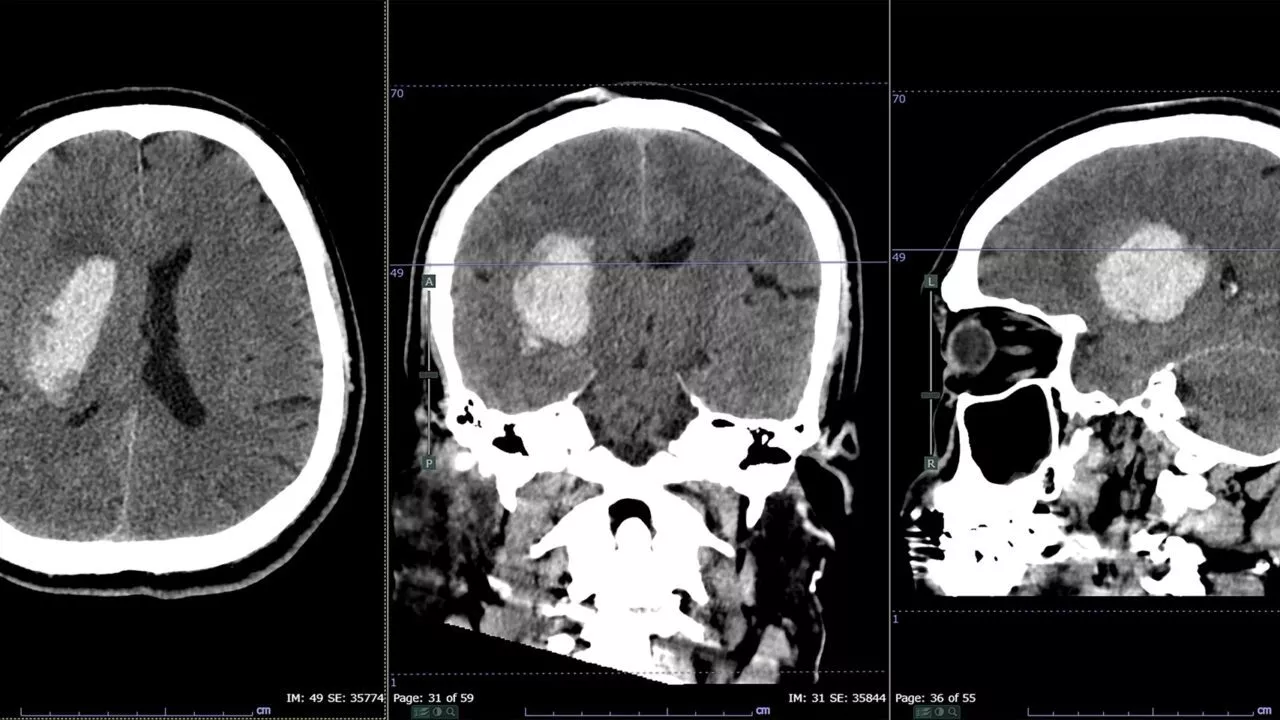

Ifølge tal fra Sundhedsstyrelsen fra 2022 bliver cirka 12.000 danskere hvert år indlagt med et stroke - også kaldet apopleksi og slagtilfælde. Det svarer til 33 om dagen.

85 procent af tilfældene skyldes en blodprop i hjernen, mens de sidste 15 procent skyldes en blødning i hjernen. Det svarer til omkring 1.800 danskere.